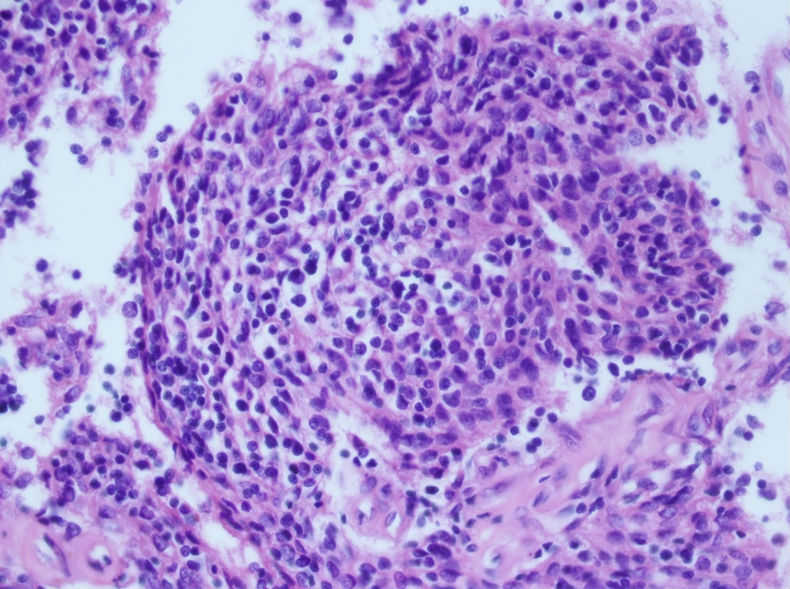

术后病理示:胸腺瘤(B3型为主)

根据腊块及免疫组化结果,我诊断了

(左胸壁)转移性胸腺瘤(B2型)

建议检查纵隔。

随访,纵隔发现一3.5×3cm肿块,术后病理示:胸腺瘤(B3型为型)

我当时就让病人等两天,等我把细胞腊块的结果出来后告诉他。

细胞腊块图片如下:

免疫组化结果:

随访,纵隔发现一3.5×3cm肿块,术后病理示:胸腺瘤(B3型为主)

肋间肿块切除的标本有的,形态和细胞腊块一致,属于胸腺瘤B2+B3型。